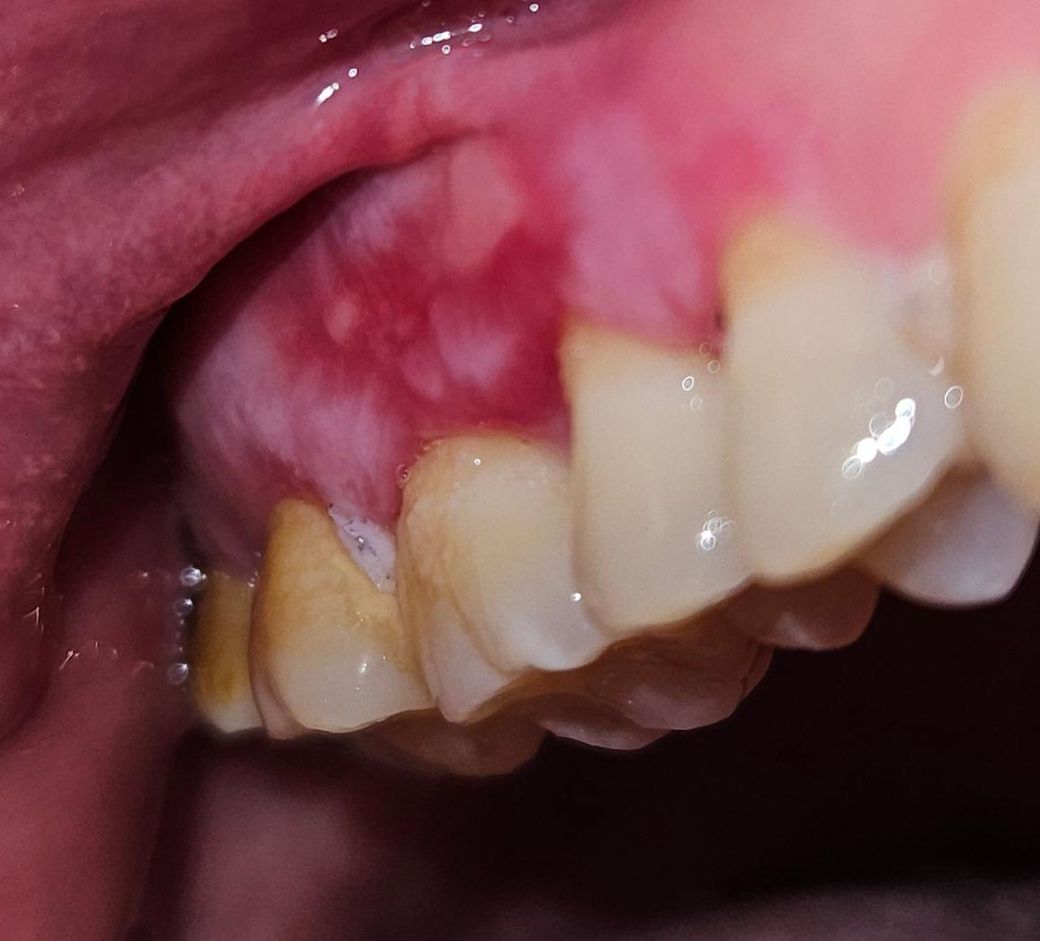

잇몸에 전반적으로 이러한 병변이 나타나고 있습니다

2개월정도 지속이 되고 있고 통증과 양치질할때 출혈이 나타나고 있습니다 치과에서는 면역력 문제라고 하는데 다른문제가 있는건 아닐까요?

• 1번 째 사진